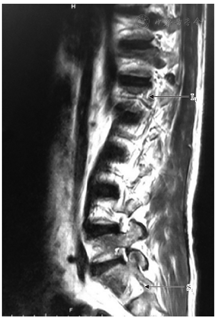

患者入院时常规对其疼痛程度进行视觉模拟评分(visual analogue scale, VAS)为8分。入院后进一步完善相关辅助检查(详见表1),(1)尿常规结果显示潜血+,25 Cells/μl;尿蛋白++,1.0 g/L;尿葡萄糖+++,28 mmol/L;(2)生化全项显示碱性磷酸酶436 U/L,磷0.56 mmol/L,钾3.33 mmol/L;(3) 24 h尿磷定量19.82 mmol/L,24 h尿钙14.21 mmol/L,24 h尿蛋白定量2.05 g/d,尿蛋白0.76 g/L;(4)尿蛋白电泳示显示混合型蛋白尿,以肾小管型为主;(5)内分泌六项显示促黄体生成素11.95 mIU/ml,促卵泡生成素21.19 mIU/ml;(6)甲状腺功能三项正常;(7)腰椎MRI显示T3~L11椎体有改变,考虑压缩骨折,各椎体信号普遍偏低,建议进一步检查除外骨髓异常疾病(图1);(8)全身骨显像显示全身多发骨质异常,性质待定(图2);(9)双下肢肌电图显示L4~S1神经根及支配区呈神经源性损害且以L4~5较为显著,合并周围神经性受损,左侧为重;(10)肿瘤全项、甲状旁腺激素、骨髓瘤监测均未见明显异常,血清免疫固定电泳未见M蛋白;(11)骨髓穿刺活检术检查显示粒细胞、红细胞、巨细胞系增生,未见明显异常骨髓象。双肾彩超未见明显异常。

注:L1椎体变扁;T11~T12、L2~T3椎体不同程度双凹变形,其内可见长T1短T2信号,脂肪抑制序列呈高信号;各椎体信号普遍偏低;椎间盘未见异常;脊髓圆锥内未见异常信号影;椎旁软组织无明显肿胀